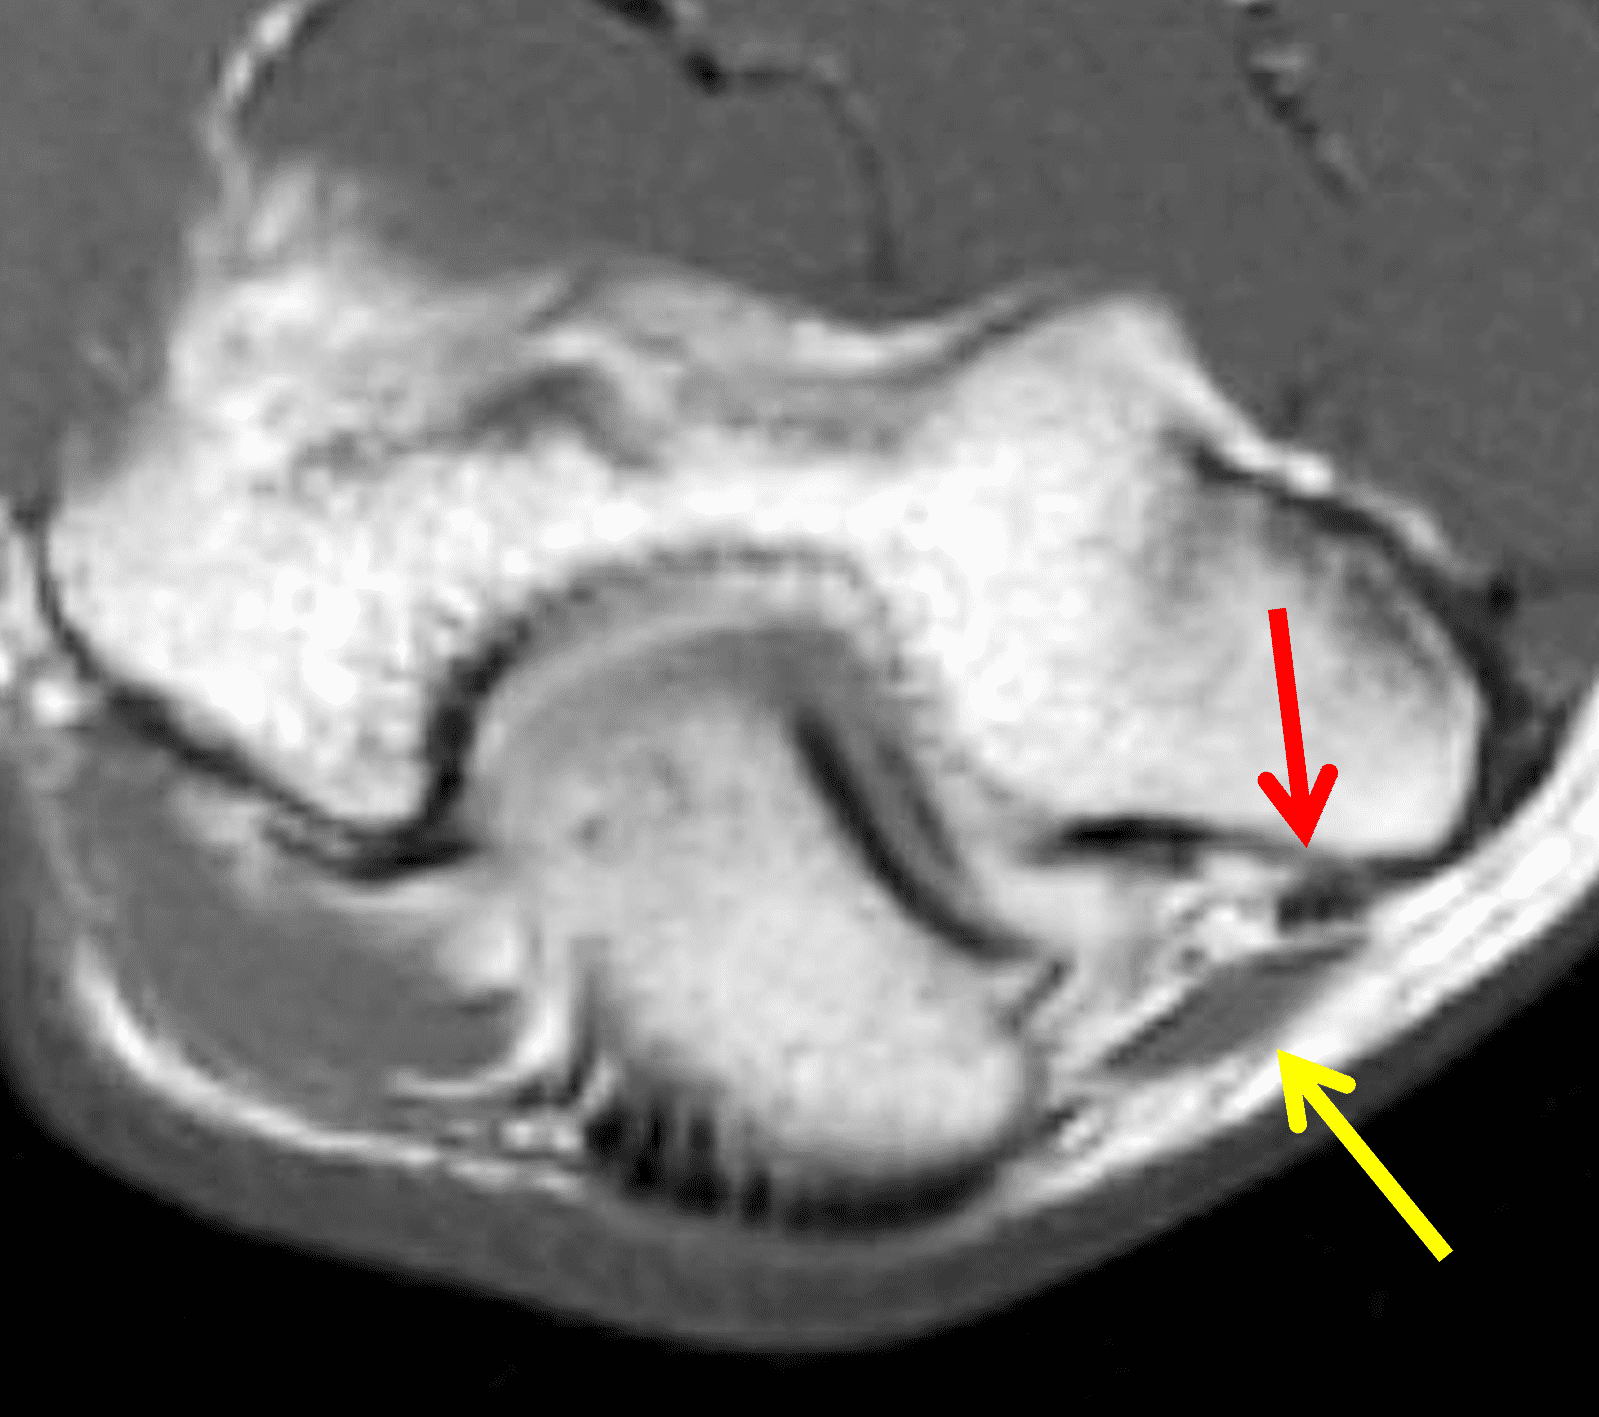

Figure 7: Absent cubital tunnel retinaculum. (7A) Drawing depicts absence of the retinaculum overlying the cubital tunnel contents. Compare with Figure 3B. (7B) Axial T1-weighted image with the elbow extended shows a normally-positioned ulnar nerve (arrow) with no defined retinaculum extending from the olecranon to the medial epicondyle. In the same patient with the elbow flexed, (7C) T1-weighted and (7D) fat-suppressed, fluid-sensitive images demonstrate dislocation of the ulnar nerve (arrows) relative to the medial epicondyle (ME).

Figure 12: 16-year-old girl who reports a “snapping” sensation with elbow flexion. She has no neurologic symptoms. Axial (12A) T1-weighted and (12B) fat-suppressed, fluid-sensitive images with the elbow extended show the ulnar nerve (arrows) normally located within the cubital tunnel. The retinaculum is either hypoplastic or absent. With elbow flexion, (12C) T1-weighted and (12D) fat-suppressed, fluid-sensitive images show the ulnar nerve (red arrows) dislocated medial to the medial humeral epicondyle. Note that a portion of the medial triceps muscle (yellow arrows) is also subluxed.